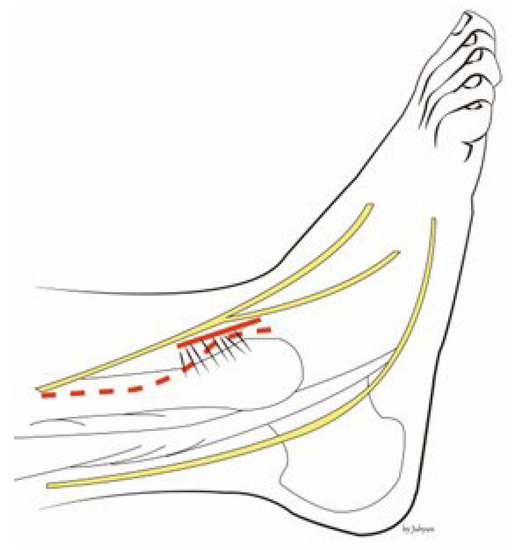

2. Surgical Technique